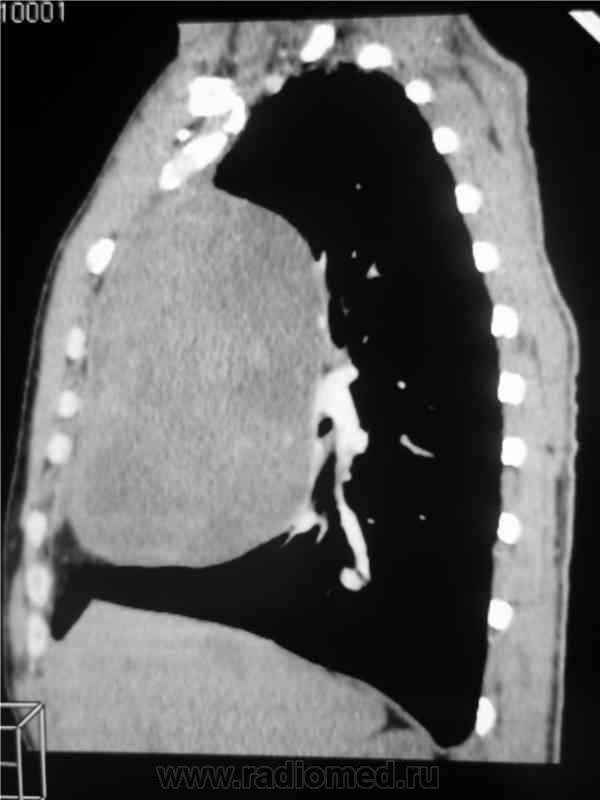

Мужчина 36 лет, рентгеногафия и КТ грудной полости.

Жалобы на субфебрильную температуру, боли в грудной клетке справа, слабость, похудание. ФГ 10 месяцев назад - норма.

КТ август 2009.

КТ контроль октябрь 2009

Интенсивное, однородное затемнение в средних отделах справа, слева норма - мною был заподозрен м/долевой плеврит, пациент был направлен в областной центр торакальной хирургии. Затем онкодиспансер, затем институт рака в Киеве. Результат гистологии тератобластома средостения. 2 курса химиотерапии контрольное КТ в октябре - отрицательная динамика.

Массивное неоднородное мягкотканное новообразование, исходящее из верхней или средней трети переднего средостения, оттесняет крупные сосуды вправо и кзади. По локализации должна быть злокачественная тимома. Хотя и лимфому наверное, не стоит отбрасывать, Ходжкинская маловероятна.